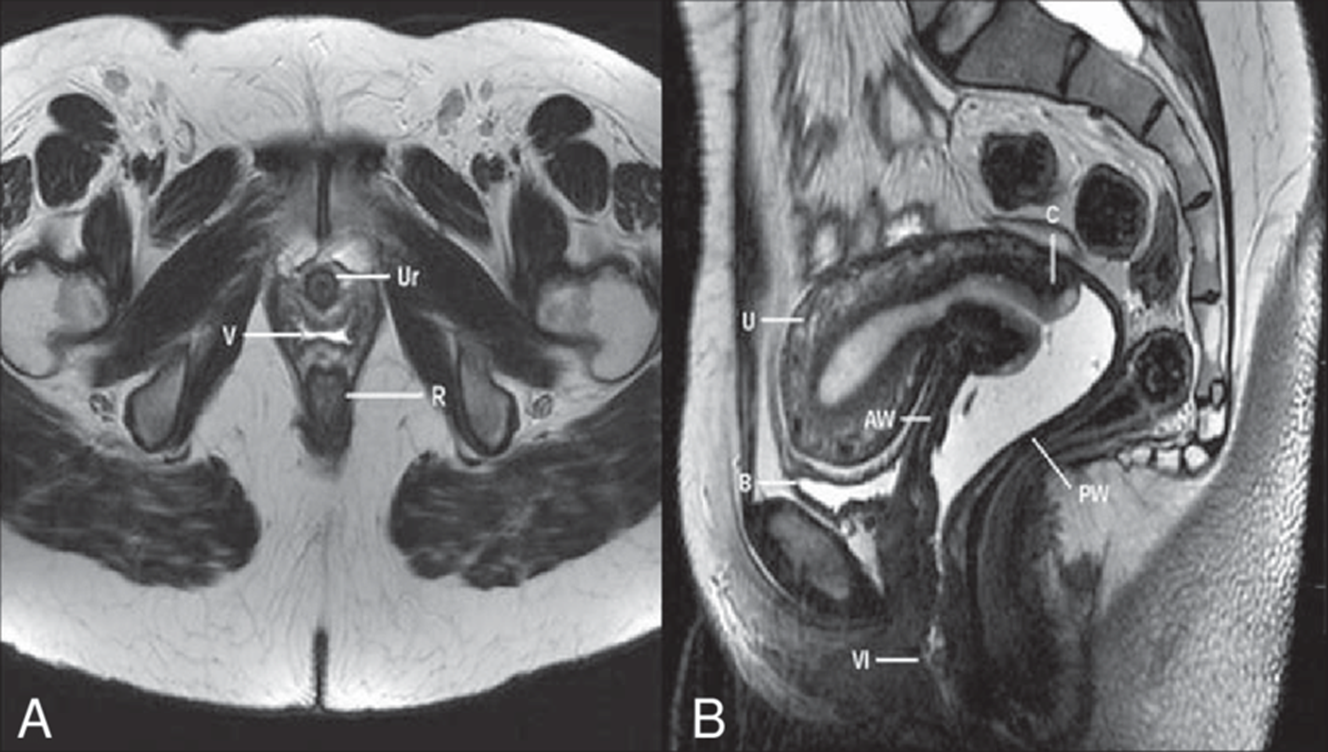

Pelvic MRI

A pelvic MRI scan specifically helps your doctor to see the bones, organs, blood vessels, and other tissues in your pelvic region—the area between your hips that holds your reproductive organs and numerous critical muscles. It can help find problems such as tumours in the ovaries, uterus, prostate, rectum, and anus. If you are pregnant, MRI may be used to safely monitor you or your baby. Excellent modality to diagnose endometriosis as MRI is sensitive to blood products.